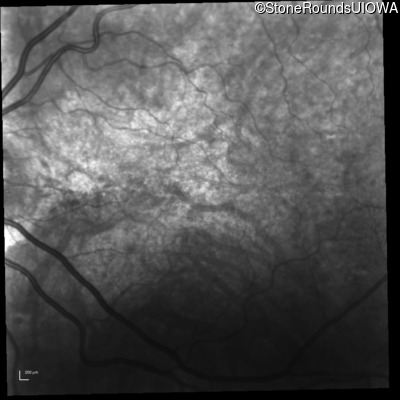

Fluorescein Angiography - Right - 20/20 -3 sc

Exemplar